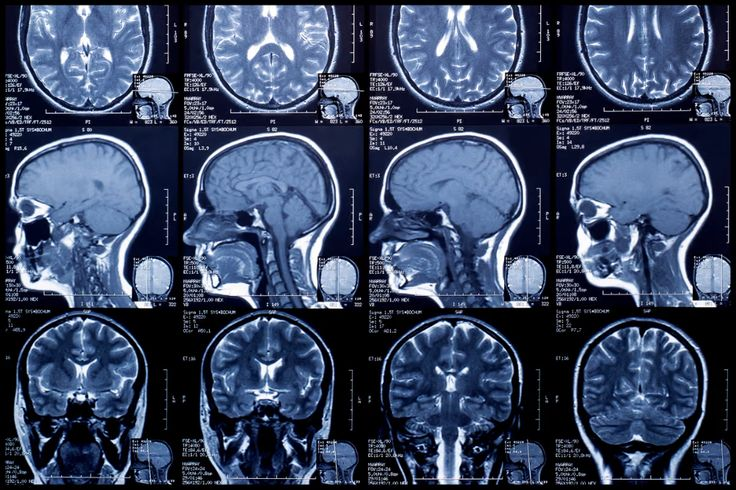

Прогнозирование возраста мозга с помощью структурной магнитно-резонансной томографии

Возраст мозга, определяемый по структурным магнитно-резонансным изображениям, обычно используется в качестве биомаркера биологического старения и здоровья мозга. В идеале возраст мозга как клинически полезный биомаркер должен указывать на текущее состояние здоровья и прогнозировать возникновение заболеваний и пагубных изменений в биологии мозга в будущем.